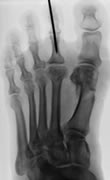

Die verkürzten Sehnen und die Gelenkkapsel werden durchtrennt, verlagert oder verlängert. Ggf. muss ein Teil des Mittelgelenks entfernt werden. Die Lücke füllt sich dann mit Bindegewebe. In manchen Fällen muss die Zehe auch vorübergehend mit einem Draht stabilisiert werden.